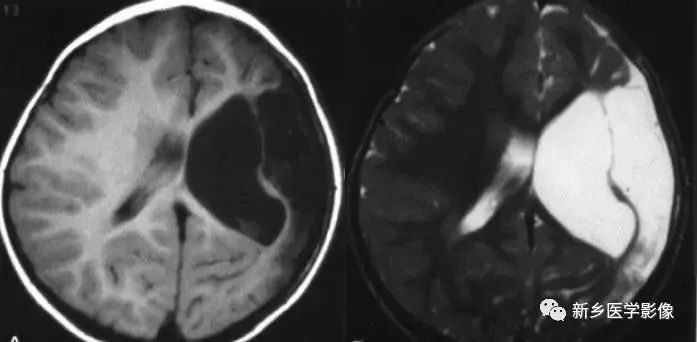

侧脑室局部扩大

❶ 局限性脑萎缩

外伤后脑萎缩、感染后脑萎缩、脑梗死后脑萎缩:

CT可见扩大的脑室部分附近的脑实质呈片状低密度灶;MR可见T1WI呈低信号,T2WI呈高信号。同时脑沟及蛛网膜下腔增宽。